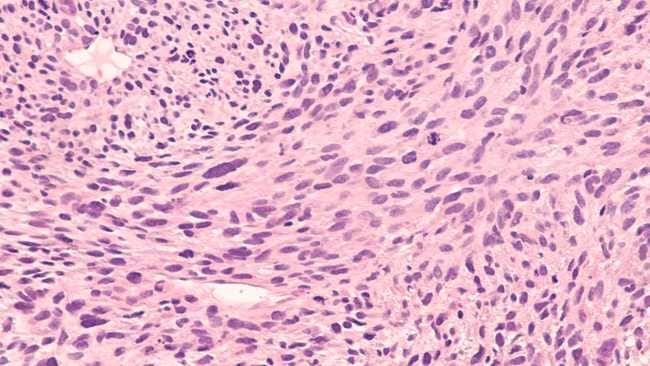

Diagnosis kanker jaringan lunak umumnya diawali dengan pemeriksaan fisik untuk menilai benjolan atau gejala yang mencurigakan. Setelah dicurigai tanda-tanda sel kanker, dokter akan menyarankan pasien untuk menjalani pemeriksaan penunjang, seperti USG, MRI, atau CT scan, guna mengetahui lokasi, ukuran, dan karakteristik tumor secara lebih detail.

Selain itu, dokter mungkin akan melakukan biopsi, yaitu pengambilan sampel jaringan dari benjolan untuk diperiksa di laboratorium. Setelah diagnosis ditegakkan, dokter dapat menentukan penanganan terbaik berdasarkan ukuran, lokasi, jenis, serta tingkat keganasan kanker jaringan lunak.